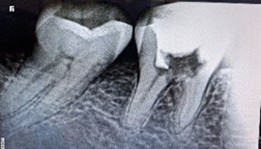

A 51-year-old woman presented with a 15-day history of persistent pain in the right mandibular posterior region. Her dental record showed multiple failed restoration attempts and an incomplete root canal on tooth 46, yet her symptoms persisted. Clinical examination and intraoral periapical radiography revealed furcation involvement, a large periapical radiolucency, and a perforation in the pulp chamber floor.

Despite a guarded prognosis for tooth survival, we performed thorough canal disinfection and placed Metapex as an intracanal medicament for four weeks. The patient reported no inter-appointment discomfort. At the subsequent visit, radiographs confirmed complete resolution of the periapical lesion, and root canal obturation was successfully completed.

Figure 1: Pre operative IOPA wrt 46 showing incomplete root canal treatment, with furcation involvement, a large periapical lesion and perforation of pulp chamber floor.

Figure 1: Pre operative IOPA wrt 46 showing incomplete root canal treatment, with furcation involvement, a large periapical lesion and perforation of pulp chamber floor. Figure 2: Metapex placement after thorough canal disinfection.

Figure 2: Metapex placement after thorough canal disinfection. Figure 3: Post 4 weeks, complete resolution of periapical lesion.

Figure 3: Post 4 weeks, complete resolution of periapical lesion. Figure 4: Post obturation IOPA after 4 weeks.

Figure 4: Post obturation IOPA after 4 weeks.